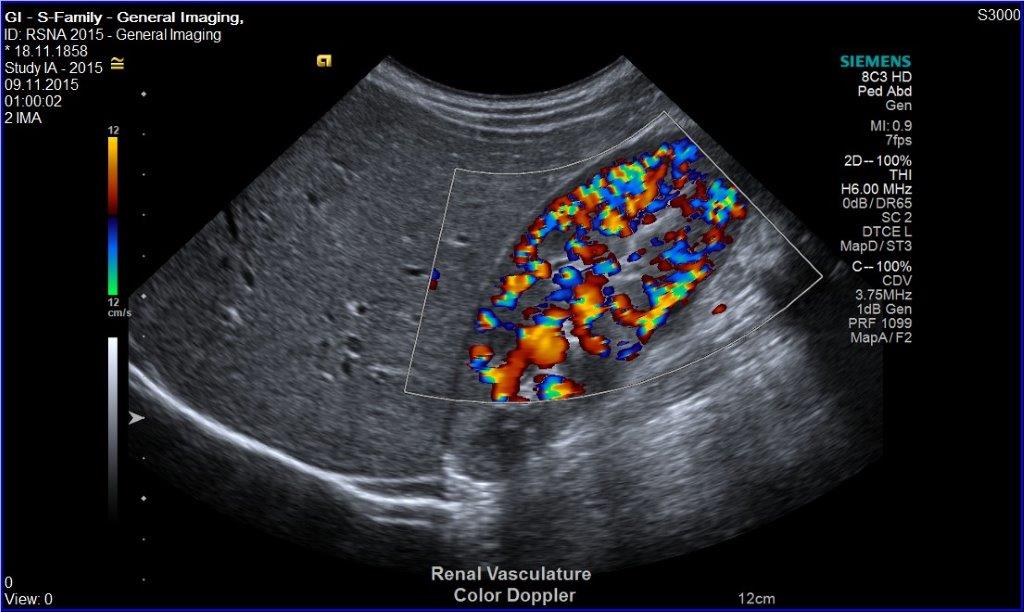

• Nieren

• Gefäßultraschall